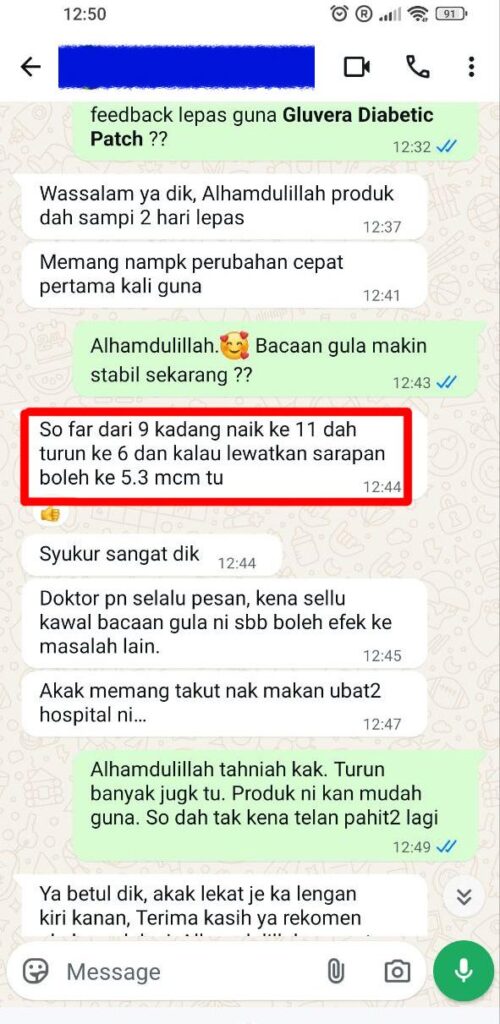

Individual results may vary, and testimonials are not claimed to represent typical results.

All testimonials are by real people, and may not reflect the typical purchaser’s experience, and are not intended to represent or guarantee that anyone will achieve the same or similar results.